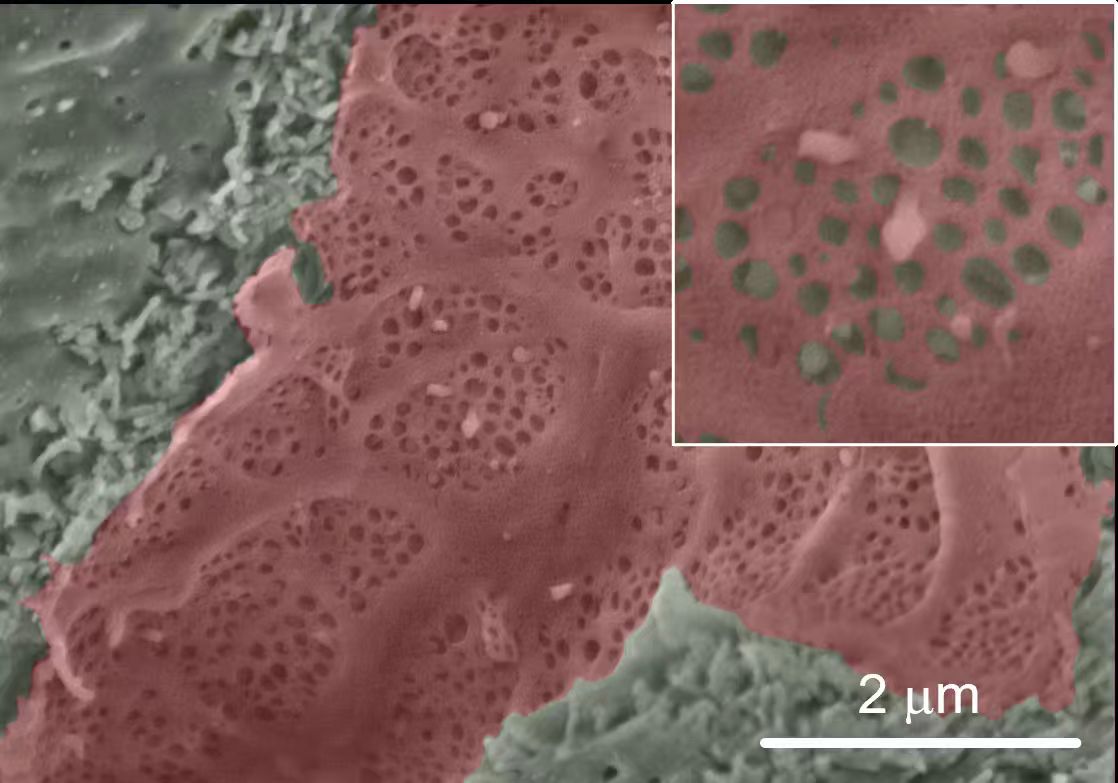

T cells migrating to the lower chamber in the Transwell experiment shown by scanning electron microscopy. -by Quanyin Gu

We systematically investigate the in vivo behavior and fate of drug delivery systems using advanced imaging and analytical tools, including intravital fluorescence microscopy, transmission electron microscopy, and synchrotron radiation-based imaging. Our studies focus on how delivery systems interact with physiological and immune barriers, such as the mononuclear phagocyte system (especially in the liver and spleen), vascular endothelium, and immune cell subsets. We analyze circulation kinetics, biodistribution profiles, cellular uptake mechanisms, and clearance pathways to elucidate the principles that govern delivery efficiency and target-site accumulation. These mechanistic insights guide the rational optimization of carrier design to improve therapeutic precision and minimize systemic toxicity.